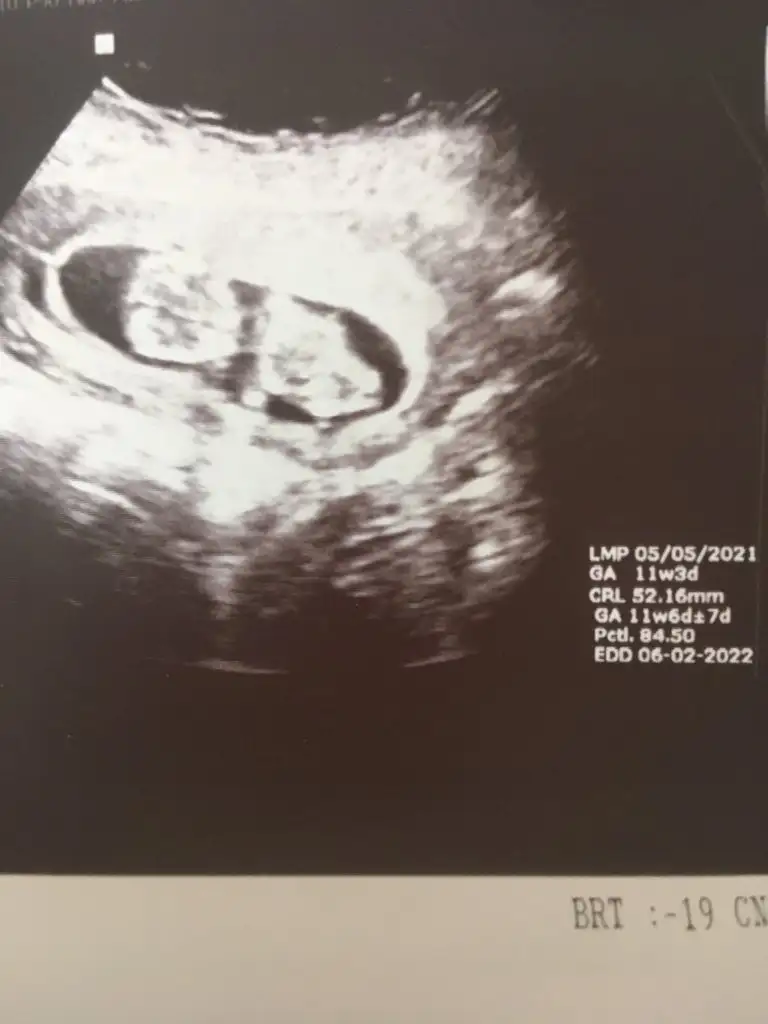

Kız gibi sanki emin olamadımEki Görüntüle 2892053 Eki Görüntüle 2892054 @Ikra meyra acaba müsait olunca bakar mısın? 11+6 oldu belli olur mu biraz?

Teşekkür ederimKız gibi sanki emin olamadım

Bugün cinsiyetini öğrendik,kızımız olacak. Teşekkürler zaman ayırdığınız için.Erkek gibi sanki